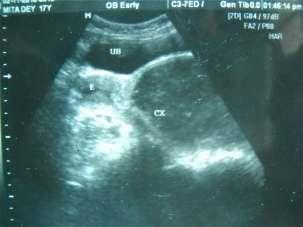

Based on the above criteria, 56 patients were selected in our study First of all vitals were checked. In severe epistaxis, first of all bleeding was controlled by nasal packing and patient was made haemodynamically stable. When the bleeding was controlled, detailed history of the patient was taken followed by general and otorhinolaryngology examination including thorough anterior rhinoscopy Laboratory investigations were done to rule out any systemic causes for epistaxis Investigations like haemoglobin estimation, total and differentialleucocytecount,plateletcount,ESR,bleeding time, clotting time, prothrombin time, a PTT, renal function tests, liver function tests, blood grouping were done routinely When no bleeding points were seen on anterior rhinoscopy and no systemic cause was found out; nasalendoscopywasperformedwithnasalendoscopes.

0 and 30 rigid nasal endoscopes of 2.7 mm and 4 mm diameterwereused.Lightcottonpledgetssoakedwith4% lidocainewasused.Noadrenalineorpriornasaldropswas usedandnoextrapressurewasexertedtoavoidmissingof the bleeding points.Then diagnostic nasal endoscopy was undertaken in three steps. The first step consisted of an inspection of nasal vestibule, nasopharynx and inferior nasal meatus. This was followed by an examination of sphenoethmoidal recess and superior meatus Finally, an examination of middle meatus was done. If nasal mass was found, CT scanwasdoneafterwards.

Mostpatientsinoursrudywereintheagegroupof2130 years (Fig 1). There were 15 female patients and 41 male patients. The most common cause of epistaxis was bleeding point in the crevices of the lateral nasal wall (32%),followedbybleedingulcerinthecrevicesoflateral nasal wall (16%), bleeding ulcer posterior to deviation of septum (14%), angioma in lateral nasal wall (13%), septal spur (11%), congested polyp in middle meatus (9%), angiofifbroma just posterior to middle turbinate (5%) (Table 1).All of them were treated with endoscopic nasal cautery,selectivenasalpacking,polypectomy,excisionof angioma,sphenopalatinearterycauterization,spurectomy or excision of angiofibroma (Table 2). All patients had successful control of epistaxis No significant complication or morbidity has been noted in the postoperative follow-up period of 1 year Seven patients hadanteriorepistaxisinfollowupperiodeitherduetonose picking or nose blowing.All of them were managed with conservativetreatment(Fig2&3).